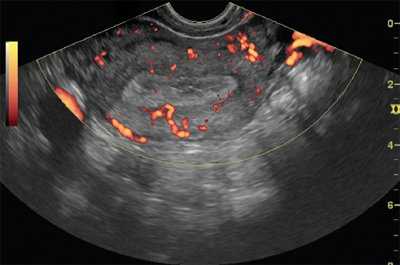

Интенсивность кровотока зависела от формы роста опухоли: при экзофитной форме отмечен интраопухолевый тип неоваскуляризации, при эндофитной - интенсивный интра- и периопухолевый тип кровотока, богатая васкуляризация миометрия (рис. 1).

Рис. 1. ТВУЗИ, режим энергетического картирования. Железисто-кистозная гиперплазия эндометрия.